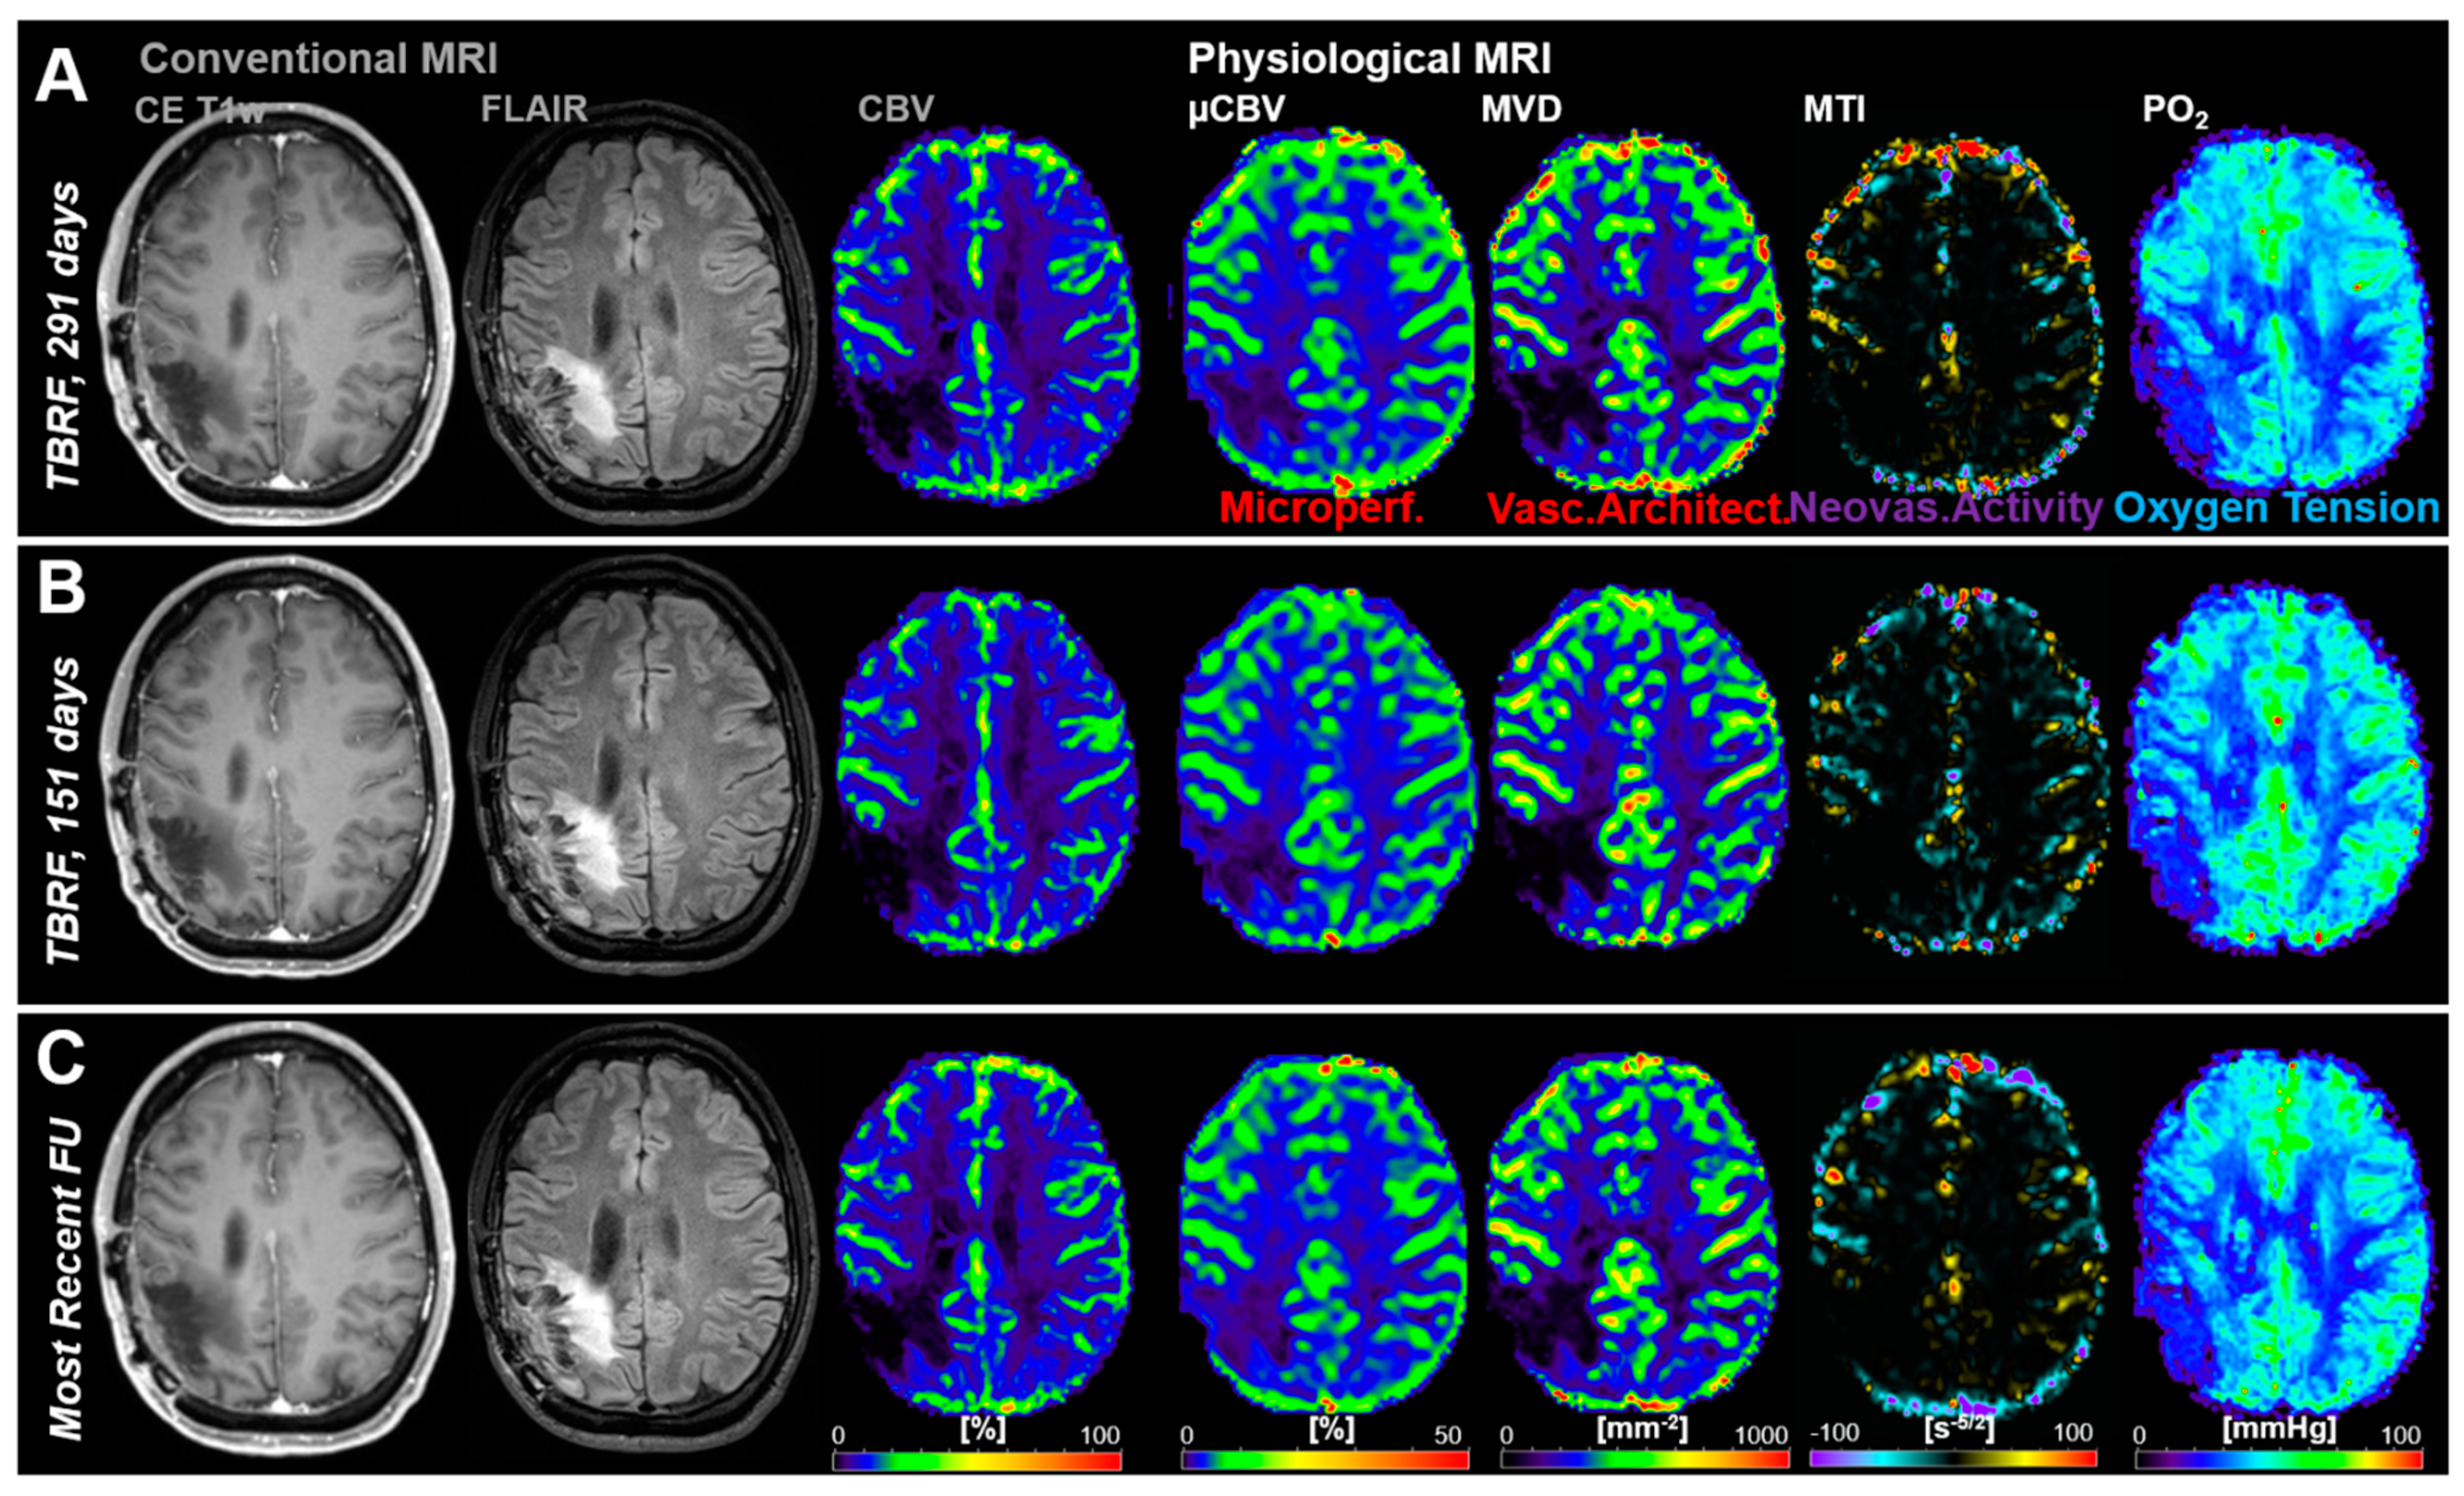

3.2. Follow-Up Examinations with Conventional and Physiological MRI

3.3. Time Courses of MRI Biomarker Changes Preceding Radiological AG Recurrence